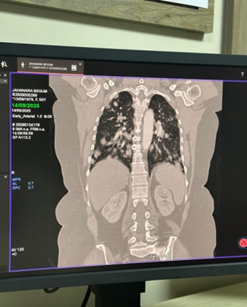

Case Presentation: A 50-year-old female presented with anorexia and cervical lymphadenopathy came for evaluation and management. Chest radiograph and CT scan demonstrated multiple bilateral pulmonary nodules without abdominal organ involvement. Core biopsy of a pulmonary lesion confirmed the diagnosis of NHL, B-cell type.

• Chest radiograph revealed multiple nodular opacities in both lung fields.

• CT chest demonstrated numerous, variable-sized nodules scattered throughout both lungs, with no mediastinal mass, pleural effusion, or consolidation.

• CT abdomen showed normal hepatosplenic and abdominal organ morphology.